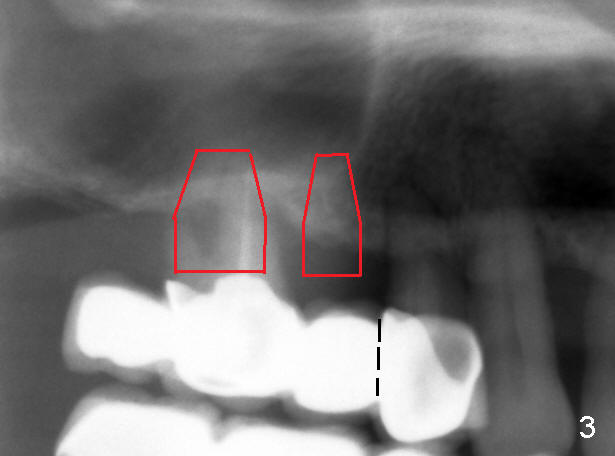

十天前我们初步讨论徐博那个疑难病例:右上4-7牙桥两到三度松动,如果问题在第一磨牙(图一:6),在4与5之间切断牙桥(图三虚线),拔除磨牙后即刻植牙(图三:大的红框)。虽然那里上颌窦底骨壁均为厚2mm左右,但是在那个磨牙牙根尤其是鄂侧根根尖处骨壁可能不止2mm,好像拱形(图二箭头,与图一对比)。所以第一磨牙处可以植入8x11mm植牙,不过需要做sinus

lift,可以完全用骨凿(从细到粗)形成植牙窝(Osteotomy),而不用钻头,这样不损失自己骨头,不需要植骨。如果时间允许,可以同时在第二双尖牙处植牙(图三:小方块,预计4 or 4.5x11mm)。